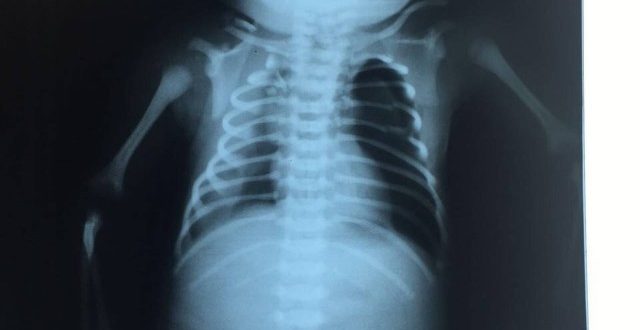

A equipe médica responsável pelo atendimento do bebê baleado na barriga da mãe na última sexta-feira disse que o quadro de paraplegia do pequeno Arthur pode ser revertido. Os médicos se reuniram nesta segunda-feira com o secretário de saúde de Duque de Caxias para uma coletiva de imprensa. O bebê foi atingido durante um tiroteio na Favela do Lixão e permanece em estado grave.

— Seria precipitado dizer se ele vai ficar paraplégico ou não. É possível que o quadro seja revertido. O foco agora é manter ele respirando e bem alimentado — disse o neurocirurgião Eduardo França, que participou da entrevista ao lado do secretário de saúde de Duque de Caxias, José Carlos Oliveira.